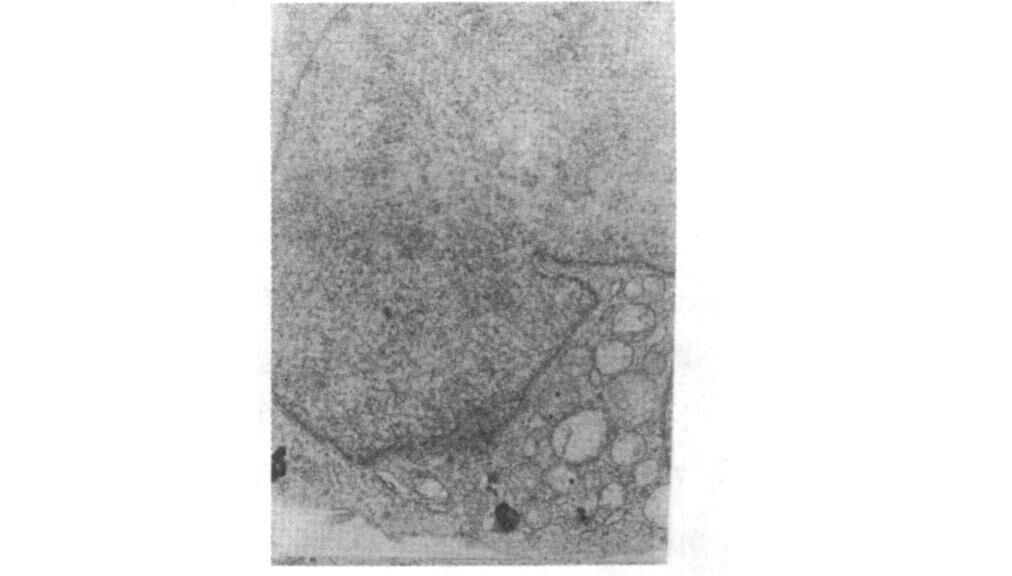

2.4 PC12细胞超微结构改变(图 1~3)假辐射组PC12细胞可见细胞核较大,染色质均匀或呈絮状,核膜间隙清楚,核仁清晰;30 mW/cm2辐射后1 d,细胞核膜间隙增宽,染色质不均,浓缩边集,核型不整,线粒体肿胀空化,内质网扩张。

图 1 假辐射组PC12 细胞电镜下超微结构(×6 300) |